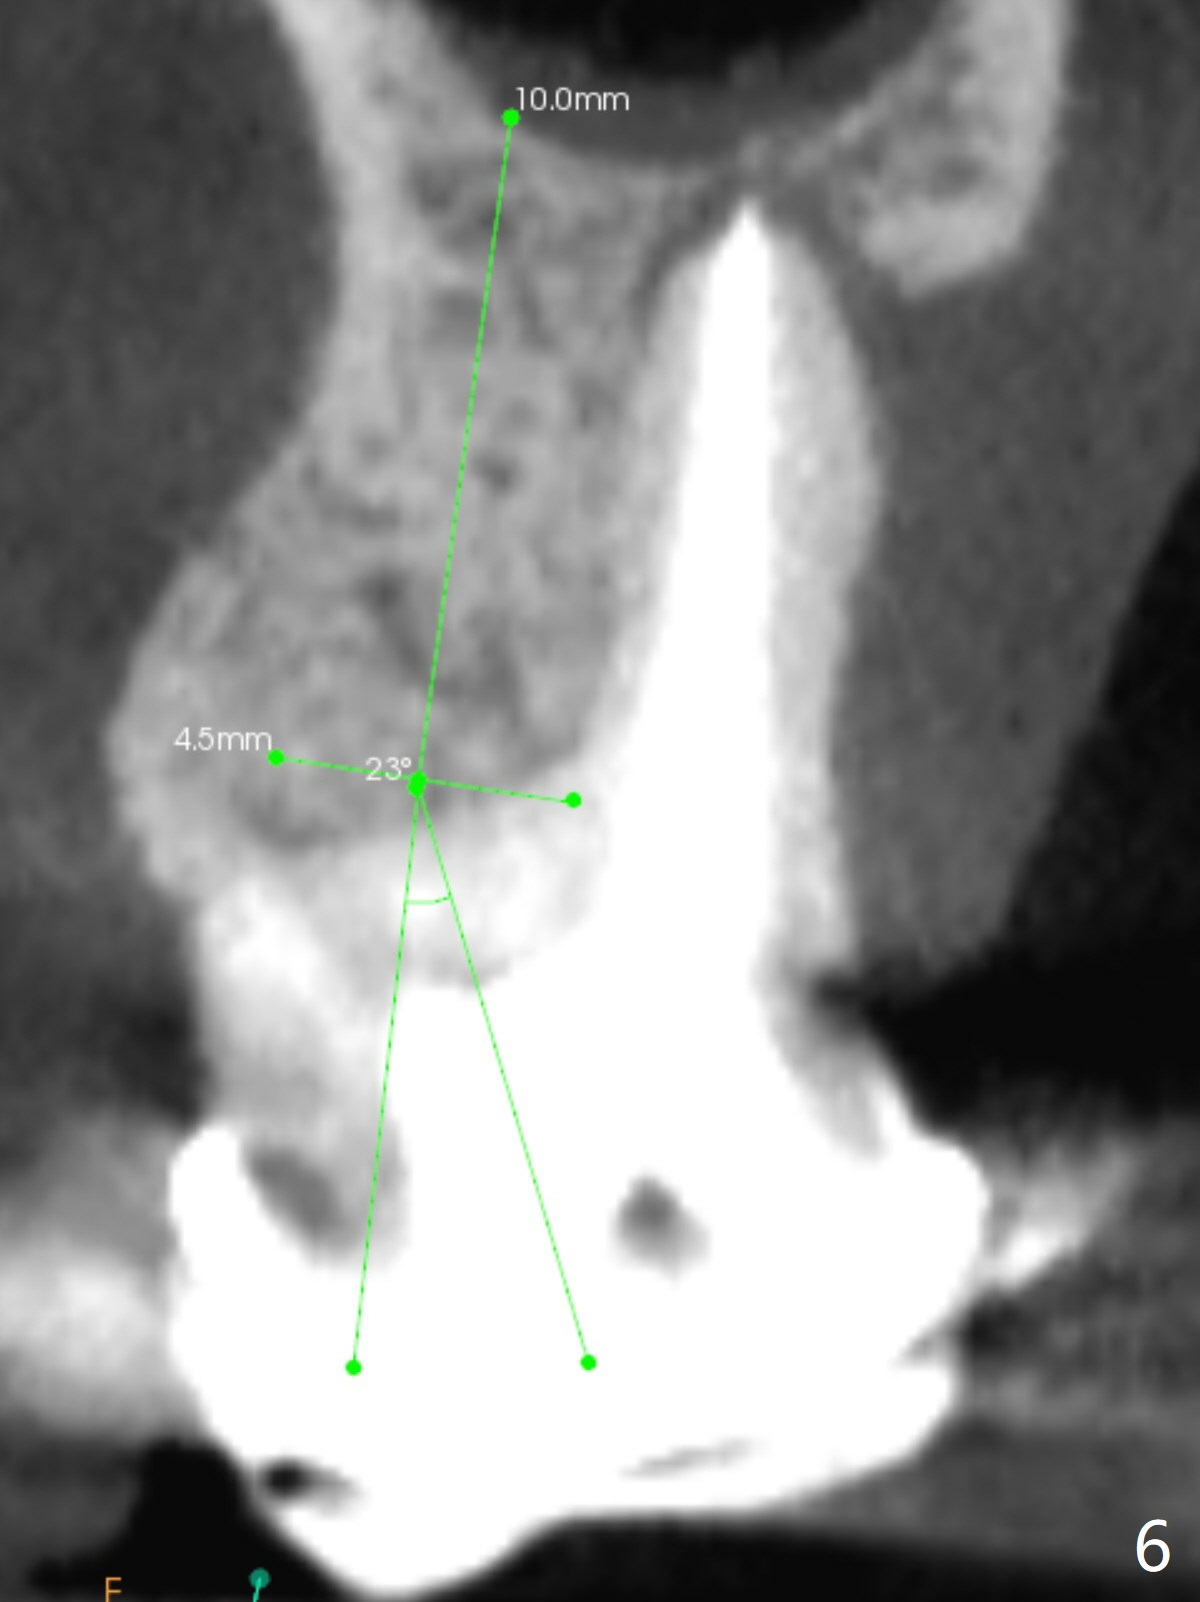

A 52-year-old woman has had chronic abscess associated with the tooth #3. The palatal root is exposed (Fig.1 P), suggesting root fracture. The apex of the mesiobuccal root seems to stick out of the buccal plate (Fig.2 *). The root canal filling is incomplete in the distobuccal root (Fig.3 *). The tooth appears to have guarded prognosis. Extraction and immediate implant is apparently a better option (Fig.4,5). It would be safer to start osteotomy in the middle of the remaining septum (Fig.6, as compared to Fig.5). After sinus lift with PRF membrane (Fig.7 yellow curved line) and implant placement (green), another piece of PRF membrane will be placed against the palatal wall of the socket, followed by bone graft (red circles) and a 25-degree angled abutment (pink).